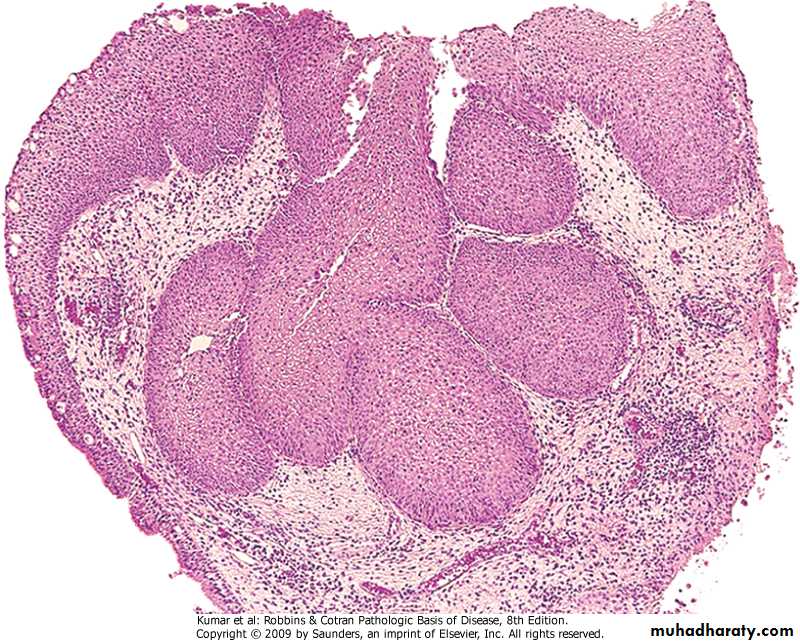

Carcinoid tumor

Low grade malignant tumor

Affect younger age group than carcinoma

Both sexes are affected equally

It form a nodule may be central or peripheral

It can metastasize

May produce vasoactive amines leading to carcinoid syndrome

Histologically consist of uniform cells

Bronchial carcinoid

Respiratory  System